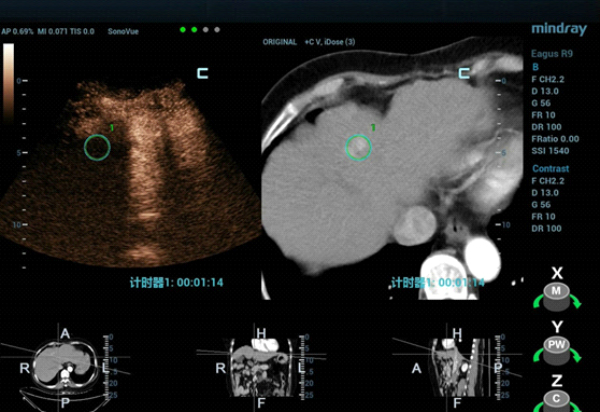

W konwencjonalnym obrazowaniu USG w skali szaro?ci nie uda?o si? uwidoczni? guza w segmencie IV zaobserwowanego w badaniu TK jamy brzusznej. W badaniu USG z kontrastem (contrast-enhanced ultrasound, CEUS) zmiana wykazywa?a wzmo?one unaczynienie w fazie t?tniczej (Obraz 2.) z izointensywnym wzmocnieniem w fazach wrotnej i pó?nej (Obraz 3.)./p>

U pacjentki zaplanowano zabieg ablacji mikrofalowej (microwave ablation, MWA) pod kontrol? USG, jednak z uwagi na fakt, ?e nie uda?o si? uwidoczni? zmiany w konwencjonalnym badaniu USG, w celu zapewnienia dok?adnego pozycjonowania elektrody mikrofalowej wykorzystano obrazowanie metod? fuzji obraz√≥w: ultrasonograficznego i TK z kontrastem (Nagranie 1, Obraz 4вАУ7).

Guz by? izoechogeniczny i nie mo?na by?o wyra?nie uwidoczni? go w badaniu USG 2D w skali szaro?ci, zatem konwencjonalna kontrola wy??cznie z zastosowaniem USG mog?a skutkowa? niedok?adnym pozycjonowaniem i niepe?n? ablacj?. Z kolei obrazowanie z wykorzystaniem fuzji obrazów uzyskanych w badaniu USG w czasie rzeczywistym z danymi uzyskanymi w badaniu TK z kontrastem umo?liwi?o dok?adne pozycjonowanie elektrody i skuteczne leczenie zmiany metod? przezskórnej MWA. Przed zabiegiem przeprowadzono badania CEUS w celu potwierdzenia umiejscowienia guza oraz po zabiegu w celu oceny obszaru poddanego ablacji i potwierdzenia skuteczno?ci leczenia.

Zastosowanie badania CEUS w po??czeniu z fuzj? obraz√≥w umo?liwia precyzyjne zlokalizowanie zmiany ogniskowej w w?trobie, dok?adne umiejscowienie elektrody mikrofalowej oraz monitorowanie i ocen? obszaru poddawanego ablacji вАУ a to wszystko w czasie rzeczywistym. Zabieg MWA pod kontrol? USG z wykorzystaniem tych dodatkowych funkcji jest bezpieczny, mo?liwy do przeprowadzenia i odpowiedni do stosowania w warunkach klinicznych.